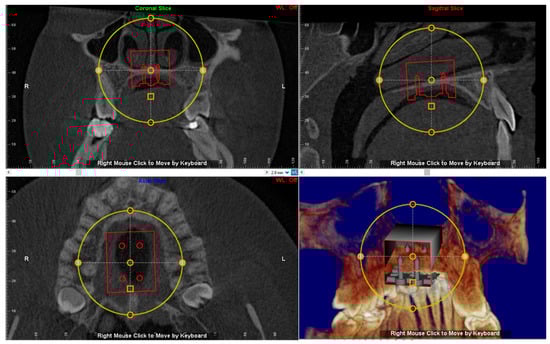

2.5. Virtual Placement of MSE (Negative Template) and Construction of the Final Lab Template

The digital model of maxillary arch is superimposed onto the CBCT DICOM file by selecting specific landmarks along the dental arch in both files (points-based registration), which allows identification of the most suitable vertical and anteroposterior placement of the MSE according to the following goals: bicortical insertion of the miniscrews, close proximity of the lower base of the MSE to the palatal mucosa and central placement of the screw using the nasal septum as visual reference (Figure 4). All these parameters were evaluated in sagittal, coronal, and axial views, and the position of the negative template of MSE was adjusted according to these parameters (Figure 5).

Superimposition of the digital model of maxillary arch onto the DICOM file for identification of the most suitable vertical and anteroposterior placement of the MSE.

The position of the negative template of MSE is determined in sagittal, coronal and axial views. See the design of the expander with the four miniscrews that are engaged in the cortical bone of the palate and nasal floor.

3.2. Digital Workflow for Planning MSE Device

The patient underwent a CBCT examination using the iCAT CBCT Unit (Imaging Sciences International, Hartfield, PA, USA) with the following parameters: 0.3 voxel, 8.9 s, small FOV (8 × 5 cm) at 100 kV and 20 mA. The distance between two slices was 0.3 mm, which provided accuracy in anatomic registration. The intra-oral scan was performed by using Trios 3 and exported in an .stl file using the Orthosystem software (3Shape A/S, Copenaghen, Denmark). Both the DICOM and 3D maxillary model files were imported to Dolphin 3D software (version 11.8.06.15 premium; Dolphin Imaging, Chatsworth, CA, USA) for registration and superimposition.

A negative template of MSE with four miniscrews was created using TINKERCAD software (Version 4.10, AUTODESK, San Rafael, CA, USA), according to the procedure above mentioned (Figure 3a–c). The negative MSE template was imported into Dolphin 3D software to be virtually placed in the palate. In this regard, the position of the negative MSE template was adjusted in order to reach bicorticalism of all the four miniscrews, the close proximity of the lower base of the MSE to the palatal mucosa, central placement of the screw using the nasal septum as a visual reference, the parallelism between miniscrews and nasal septum (Figure 4and Figure 5).